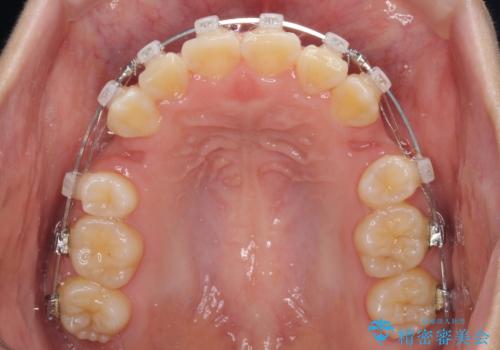

- クリアブラケット

- 2年1ヶ月

- 10-30回